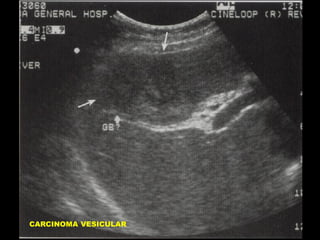

APARIENCIA ECOGRAFICA DEL

CARCINOMA DE VESICULA

•

Masa intraluminal

Engrosamiento mural asimétrico

Masa reemplazando la Vesícula

Calcificación de la pared Vesicular

Colelitiasis

Metástasis Hepáticas

Adenopatías

Dilatación de la via biliar

CARCINOMA VESICULAR

Carcinoma primario vesicular

Engrosamiento asimétrico de pared